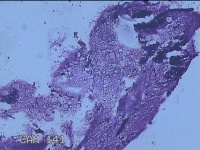

性别

男

年龄

40岁

临床诊断

混合痔

一般病史

反复肛门肿物突出15年。

标本名称

肛门肿物

大体所见

灰白暗红色肿物0.7x0.5x0.2cm一个,表面糜烂。

图1

脱水、透明,浸蜡、脱蜡效果不佳,制片质量差。